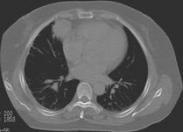

按致伤原因和伤情分类 可分为:①闭合性损伤,是胸部受暴力撞击或挤压所致的胸部组织和脏器损伤,但胸膜腔与外界大气不直接相通。常见的致伤原因有挤压伤、钝器打击伤、高空坠落伤、爆震伤等。轻者只有胸壁软组织挫伤或单纯性肋骨骨折,重者可有内脏损伤(主要是心肺损伤)、多处肋骨骨折,并可引起气胸、血胸、纵隔或皮下气肿、损伤性窒息及膈疝等。爆震伤是爆炸产生的强大气流冲击波作用于胸部而引起胸内脏器(主要是肺脏)的损伤,主要见于战时,平时可见于工矿爆炸事故。偶可由于吸入火焰、高热气体或蒸气而伴有呼吸道烧伤。胸部闭合性损伤的严重程度取决于受伤组织或器官的数量和伤情,以及有无胸外合并损伤。②开放性损伤,损伤穿破胸膜,使胸膜腔与外界相通,造成气胸、血胸或血气胸,有时还可穿破膈肌或伤及腹内脏器。主要见于战时的火器伤,在平时多为锐器刺伤。